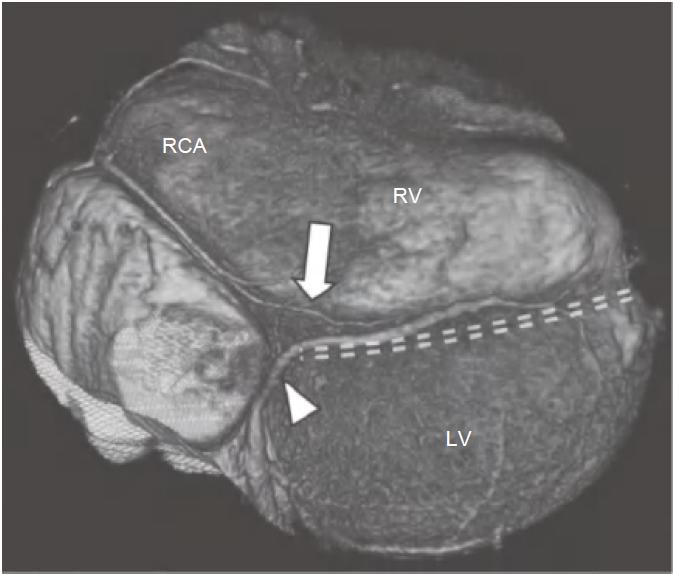

图13-2 左旋支(箭)起自左主干分叉处,并沿LAVG(虚线)走行,为左心室侧壁供血

AO.主动脉;PA.肺动脉;RV.右心室;LV.左心室